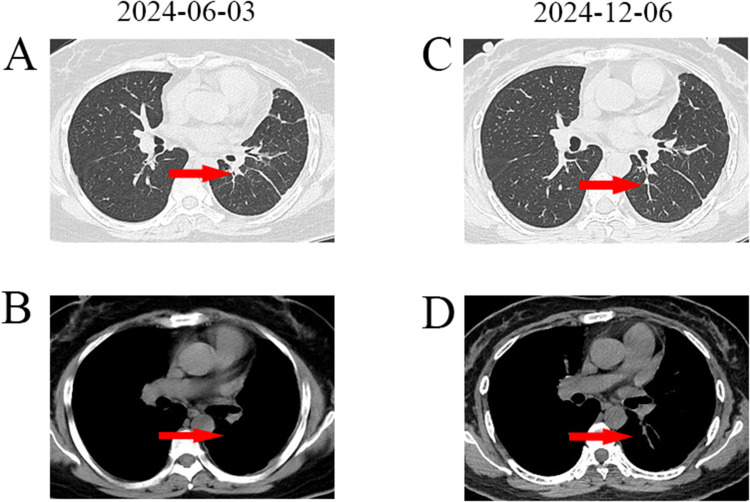

奥西替尼已成为表皮生长因子受体(EGFR)突变晚期非小细胞肺癌(NSCLC)一线治疗的标准药物。尽管先前的研究报道BRAF V600E突变是对奥西替尼的独特耐药机制,但同时携带EGFR和获得性BRAF-V600E突变的肺腺癌患者的治疗尚不清楚。在这里,我们报告一例36岁的女性被诊断为IV期肺腺癌,携带EGFR L858R突变。她接受了24个月的奥西替尼治疗,并经历了疾病的进展。重新活检病理显示肺病变仍为腺癌,NGS显示除EGFR L858R突变外,还增加了BRAF V600E和TP53突变。该患者随后接受奥莫替尼联合达非尼和曲美替尼治疗,8个月后完全缓解。总之,获得性BRAF-V600E突变可能导致奥西替尼耐药。奥莫替尼加BRAF抑制剂改善了奥西替尼治疗失败的EGFR-L858R和获得性BRAF- v600e突变性肺腺癌患者的预后。

Osimertinib has become the standard of care in the first-line treatment of advanced non-small cell lung cancer (NSCLC) harboring epidermal growth factor receptor (EGFR) mutations. Although previous studies reported that the BRAF V600E mutation is a unique resistance mechanism to osimertinib, the treatment of lung adenocarcinoma patients harboring both EGFR and acquired BRAF-V600E comutations remains unclear. Here, we report a case of a 36-year-old woman diagnosed with stage IV lung adenocarcinoma harboring the EGFR L858R mutation. She received osimertinib for 24 months and experienced progressive disease. Rebiopsy pathology revealed that the lung lesion was still adenocarcinoma, and NGS revealed gains of BRAF V600E and TP53 mutations in addition to the EGFR L858R mutation. This patient subsequently received aumolertinib in combination with dabrafenib and trametinib and achieved a complete response for 8 months. In conclusion, acquired BRAF-V600E mutations may contribute to osimertinib resistance. Aumolertinib plus BRAF inhibitors improves outcomes in patients with EGFR-L858R and acquired BRAF-V600E comutant lung adenocarcinoma in whom osimertinib treatment has failed.